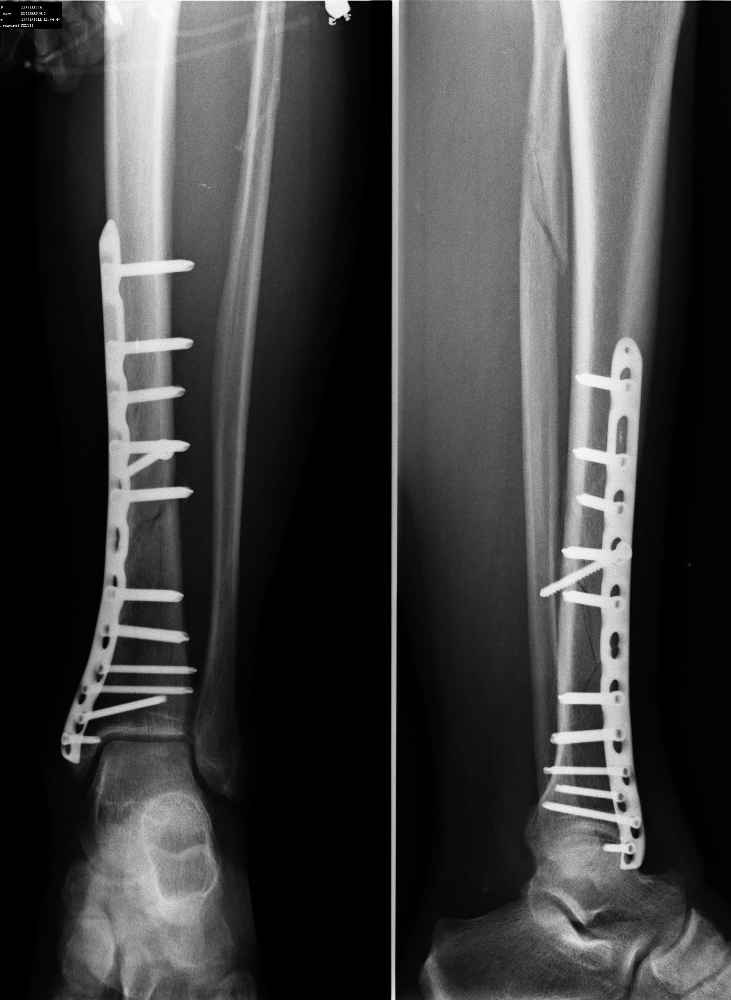

А что беспокоит пациента? При остеосинтезе пластинами LCP в проксимальном и дистальном отломках нужно было ввести в 2 раза меньше винтов. Если сейчас удалить часть винтов и дать частичную нагрузку на ногу, то я думаю процес консолидации пойдет веселее.

Отломки идеально сопоставлены. Остеосинтез стабильный. В такой ситуации должно наступать первичное сращение практически без образования мозоли. Ориентироваться при оценке степени консолидации нужно на завуалированность линий перелома и нарастание, при неблагоприятном развитии ситуации, регионарного остеопороза, которого пока нет, а не на наличие и величину костной мозоли. И нагрузку через такой срок можно уже практически полную давать.

согласен с Михаилом, надо дать дозированную нагрузку, это улучьшит питание конечности. А кость надо жалеть и столько не крутить винтов, шанс на атрофический ложняк велик. Стягивающий 4,5 мм винт не работает, а 5,0 мм LSP распирает линию перелома.

Остеосинтез достойный. Единственное не стоит оставлять пустое отверстие в проекции перелома, но к данному вопросу это никакого отношения не имеет. Нагрузка, динамическое наблюдение.

о замедленной консолидации говорить однозначно рано, беспокоиться практически не о чем

самый дистальный шуруп насквозь через внутреннюю лодыжку в сустав ( см увеличенный рисунок). Хорошо было бы его убрать - стабильности остеосинтезу он совершенно не добавляет.

Показательный пример оиспользоания технологии при отсутствии понятий. Скорее всего выполнено скелетирование кости с разрушением периостального кровоснабжения, а вид перелома говорит о первично пострадавшем мадулярным кровотоке. Осталось уповать на дозорованную динамическую стимуляцию заживления кости и прочность конструкций.